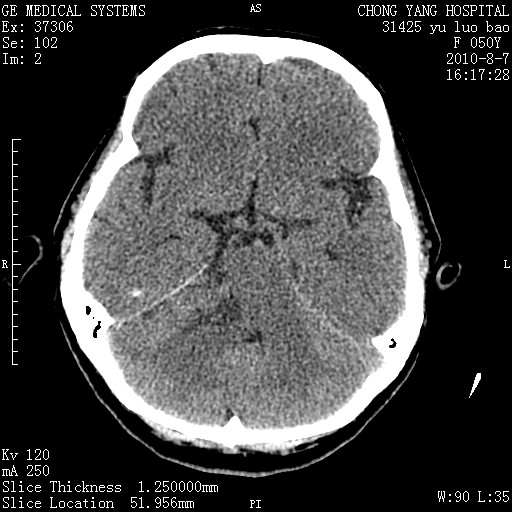

标题: CT28285:听力下降一年,头昏。 [打印本页]

标题: CT28285:听力下降一年,头昏。

右侧桥小脑角区占位--听神经瘤,建议增强或mri检查。

右侧桥小脑角去等密度占位,右侧内听道扩大、骨质吸收,考虑:右侧听神经瘤,建议增强检查。

考虑右侧听神经瘤。